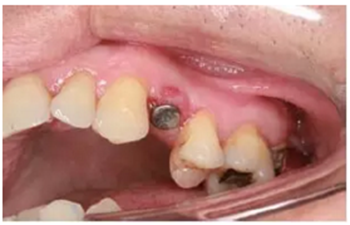

患者情況

患牙21因根管治療超充,導(dǎo)致根尖周炎,唇側(cè)齲壞并出現(xiàn)瘺管。擬采用即刻種植修復(fù)。術(shù)前拍攝CBCT并做種植方案規(guī)劃,從方案上可知唇側(cè)及遠中側(cè)骨缺損較為嚴(yán)重,需要同期進行引導(dǎo)骨再生術(shù)(GBR)。

圖9 種植方案規(guī)劃:a.近遠中方向的截面圖,唇側(cè)需要GBR;b.軸向截面圖;c. 模擬植入4.0×13 mm 的種植體